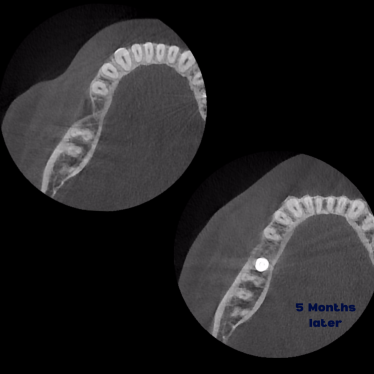

Kist nedeni ile çene kemiğinde defekt oluşmuş vakamıza sert ve yumuşak doku ogmentasyonu uyguladık